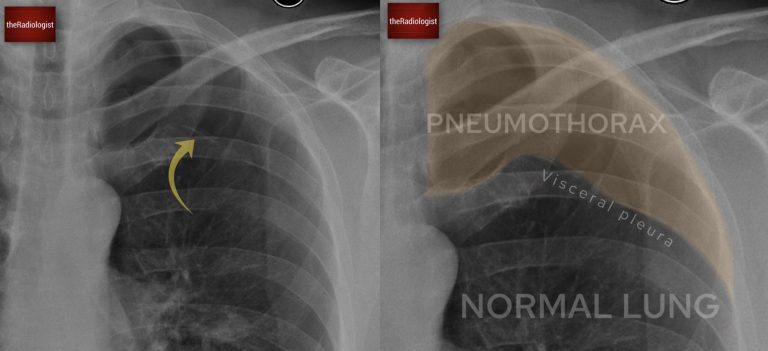

I do not consider a chest X‑ray fully reviewed until I have zoomed right in on both apices and that’s mainly because a pneumothorax can be very subtle unless you magnify the film. A pneumothorax represents gas within the pleural space – remember the pleura has two layers the visceral (inner) and parietal pleura (outer).

Pneumothorax represents gas within the pleural space, between the inner visceral and outer parietal pleura.

The two cardinal signs to look for are, firstly, a lucent black area of lung without visible vascular markings and, secondly, a thin white pleural line representing the visceral pleura separating from the parietal pleura. Compare side to side: if one apex lacks markings where the other has them, this should ring alarm bells. Bullae from emphysema can mimic a lucent pneumothorax, but these tend to be round and do not display a sharp pleural line paralleling the chest wall.

Here in this case we have the two cardinal signs of pneumothorax: one, a white pleural line (yellow arrow) and two lucency without lung markings outside of this.